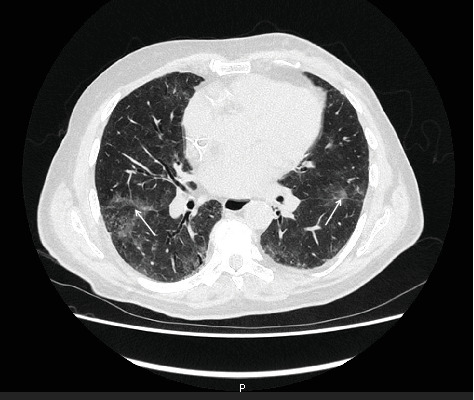

背景:耶氏肺囊虫肺炎(PJP)是免疫功能低下患者公认的机会性感染,特别是血液系统恶性肿瘤或HIV感染患者。然而,在接受化疗的实体肿瘤患者中,其发生情况仍不清楚。病例介绍:我们报告了一例84岁男性her2阳性乳腺癌患者,在紫杉醇和曲妥珠单抗辅助化疗后发生了严重的PJP。患者没有已知的免疫抑制状况,在出现症状之前没有出现化疗引起的淋巴细胞减少症。患者因3级虚弱而停止化疗9天后,因发热和呼吸困难入院。胸部计算机断层扫描(CT)显示弥漫性磨玻璃影,支气管肺泡灌洗经PCR证实有肺囊虫DNA存在。尽管及时给予磺胺甲恶唑/甲氧苄啶和皮质类固醇治疗,患者仍出现难治性急性呼吸窘迫综合征(ARDS),并于ICU入院后死亡。讨论:本病例强调了接受辅助化疗的老年患者PJP的潜在风险,即使在没有明显免疫抑制的情况下。鉴于化疗在老年人群中的使用越来越多,应考虑全面的风险-收益评估,特别是在预期生存获益有限的情况下。目前的指南不建议对实体肿瘤患者进行系统的PJP预防,但新出现的证据表明,化疗相关的淋巴细胞减少可能增加对机会性感染的易感性。结论:临床医生应保持对老年化疗患者PJP等机会性感染的高度怀疑,无论其免疫状况如何。该病例强调了个体化风险分层和警惕监测的重要性,以预防和管理危及生命的并发症。

Background: Pneumocystis jirovecii pneumonia (PJP) is a well-recognized opportunistic infection in immunocompromised patients, particularly those with hematological malignancies or HIV infection. However, its occurrence in patients with solid tumors undergoing chemotherapy remains poorly characterized. Case Presentation: We report the case of an 84-year-old male patient with HER2-positive breast cancer who developed severe PJP following adjuvant chemotherapy with paclitaxel and trastuzumab. The patient had no known immunosuppressive conditions and did not present chemotherapy-induced lymphopenia prior to the onset of symptoms. He was admitted with fever and dyspnea, 9 days after discontinuation of chemotherapy due to Grade 3 asthenia. Chest computed tomography (CT) revealed diffuse ground-glass opacities, and bronchoalveolar lavage confirmed the presence of Pneumocystis jirovecii DNA by PCR. Despite prompt initiation of sulfamethoxazole/trimethoprim and corticosteroids, the patient developed refractory acute respiratory distress syndrome (ARDS) and died after ICU admission. Discussion: This case highlights the potential risk of PJP in elderly patients receiving adjuvant chemotherapy, even in the absence of evident immunosuppression. Given the increasing use of chemotherapy in older populations, a thorough risk-benefit assessment should be considered, especially when the expected survival benefit is limited. Current guidelines do not recommend systematic PJP prophylaxis in patients with solid tumors, yet emerging evidence suggests that chemotherapy-related lymphopenia may increase susceptibility to opportunistic infections. Conclusion: Clinicians should maintain a high index of suspicion for opportunistic infections such as PJP in elderly patients undergoing chemotherapy, regardless of their immune status. This case underscores the importance of individualized risk stratification and vigilant monitoring to prevent and manage life-threatening complications.